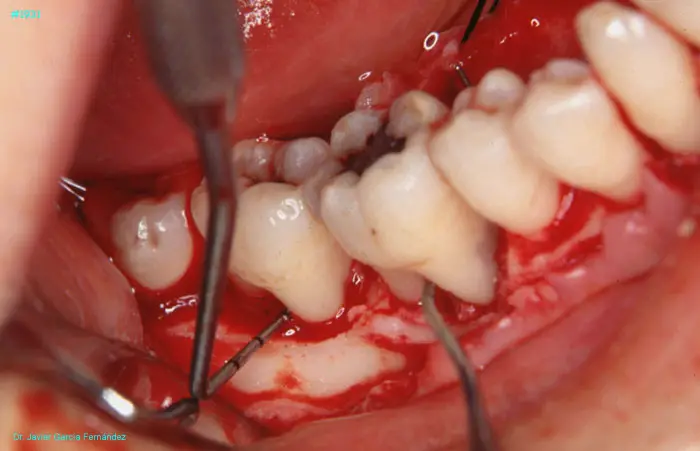

image 78